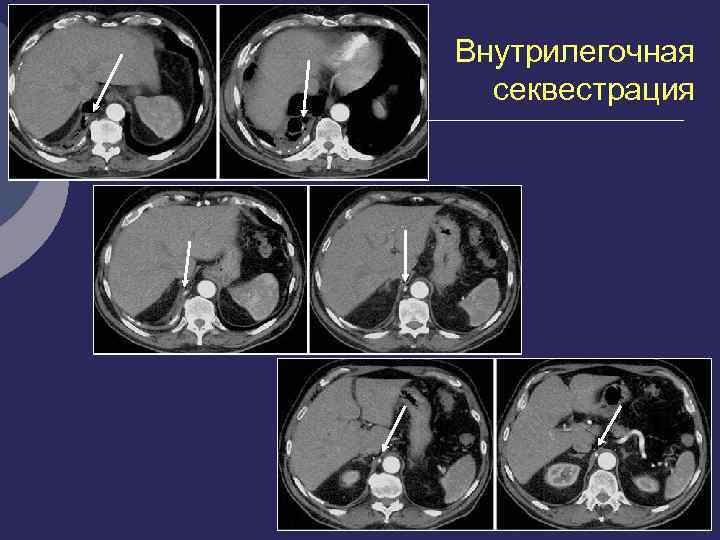

Легочная секвестрация (Pryce, 1946). Ø Порок развития, характеризующийся наличием участка легочной ткани, расположенного внутри легкого или вне его, не связанного с бронхиальной системой легкого, содержащего элементы бронхиальной и альвеолярной ткани Ø Кровоснабжение - аномальная артерия, отходящей от Ао или ее ветвей Ø Отток - в непарную или полую вену Ø 3 -6 неделя эмбриогенеза Ø 1% оперированных по поводу хроничес- ких нагноений легких

Внутрилегочная Внелегочная секвестрация Ø аномальный участок расположен Ø аберрантное легкое, доля, имеет внутри легочной ткани, висцеральную плевру Ø не имеет плеврального отграничения Ø может располагаться как внутри легкого, так и вне его. Ø Морфологически – плотный желтоватый пигментированный участок с одной или несколькими кистами. Ø Клиника – хронического нагноительного процесса. Внутридолевая Внедолевая секвесирация секвестрация

Rg-диагностика секвестрации Ø Все признаки кисты (заполненной или вскрывшейся) Ø Локализация: 80% - 10 сегмент, 12% - 10+6 сегменты 6% - 6 сегмент. , 1 -2% - средняя и верхняя доли Ø Аортография – дополнительный сосуд, отходящий от аорты или ее ветвей к кисте, обычно проходит в толще легочной связки Ø Дифференциальная диагностика: абсцесс, бронхоальвеолярная киста, новообразование, туберкулез

Внутрилегочная секвестрация